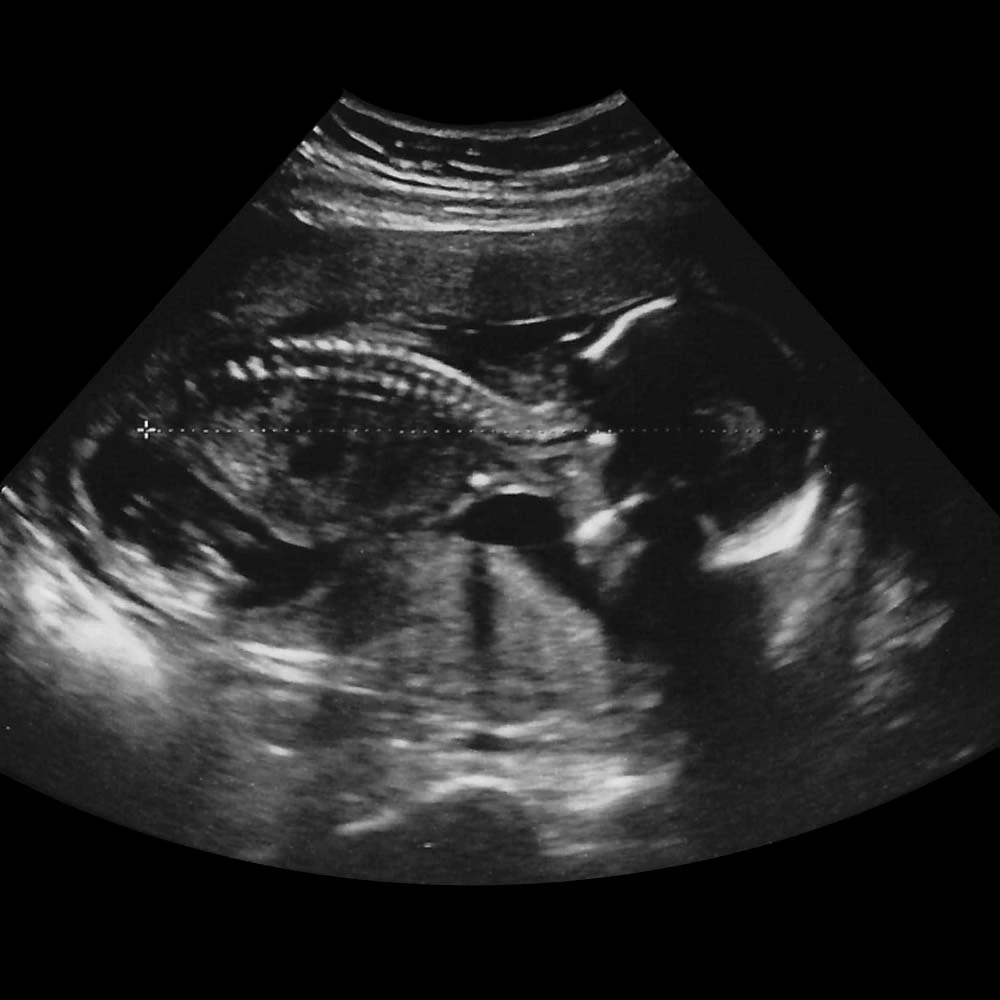

Неделя № 12

Копчиково-теменной размер плода составляет 50-60 мм.

Отчетливо идет развитие половых органов по женскому или мужскому типу.

Кишечник вытягивается в длину и укладывается петлями, как у взрослого человека. Начинается его периодические сокращения – перистальтика. Плод начинает совершать глотательные движения, заглатывая околоплодные воды.

Головной мозг имеет маленькие размеры, но точно повторяет все структуры мозга взрослого человека, плод может сжимать и разжимать пальцы в кулак, захватывает большой палец и активно его сосет.

В крови плода уже присутствуют не только эритроциты, но и начинается выработка белых кровяных клеток – лейкоцитов.

В это время у ребенка начинают регистрироваться единичные дыхательные движения. До рождения плод не может дышать, его легкие не функционируют, однако он совершает ритмичные движения грудной клетки, имитируя дыхание.

К концу недели у плода появляются брови и ресницы, хорошо заметна шея.